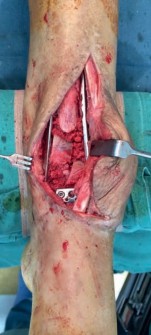

For definitive fixation, the anterolateral fragment is buttressed with an anterolateral plate and the medial fragment is buttressed with a medial plate. If the plates are longer than the incision, the plates can be slid proximally along the periosteum, and screws inserted using a minimally invasive technique. Large metaphyseal defects should be bone-grafted (Fig 2.2-5).

After pilon fracture fixation is completed, the fibula is fixed. Fibular fixation provides greater stability to the construct. The skin bridge must be considered when placing this third incision, aiming to maximize the distance between it and the vertical limb of the extensile approach and the modified posteromedial approach. The fibula is reduced anatomically and plated (Fig 2.2-6). In situations of tenuous soft tissue, the fibula can be reduced with a mini-open approach and stabilized with an intramedullary rod or screw inserted retrograde from the distal end of the fibula.

Fig 2.2-5 Intraoperative images.

1. Posterior, anterolateral, and medial plates have been applied. Anatomical reduction and stable fixation of the tibial plafond articular surface has been successfully achieved. At this stage, the fibula had not yet been fixed.

2. Lateral image shows a well-reduced tibial articular surface and a congruent tibiotalar joint.